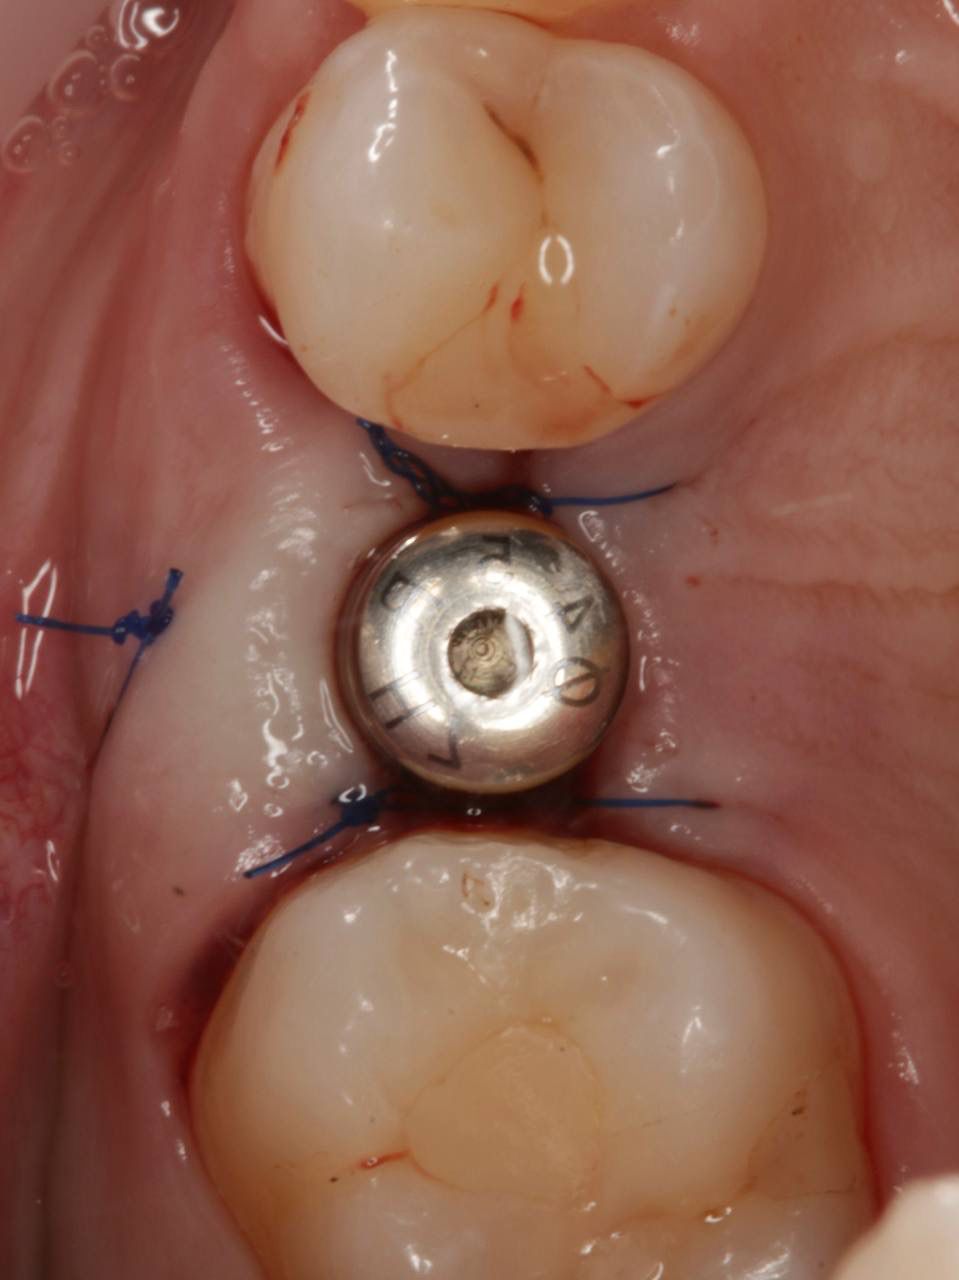

Установка импланта, подшит трансплантат с бугра( для увеличения объема мягких тканей), установлен формирователь десны

Установка импланта